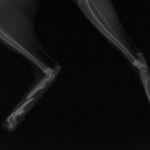

交通事故直後、胸腰部に激しい疼痛、両後肢に完全麻痺を認め、シェフシェリントン徴候を呈していました。レントゲン検査において、第11-12胸椎間の脱臼が認められました。

脊髄の減圧、脊柱管の再構築・安定化を目的に、片側椎弓切除術およびMatrixMANDIBLE Plateによる椎体固定を実施しました。

隣接椎体を架橋するようにプレートを設置しました。

術後レントゲン写真